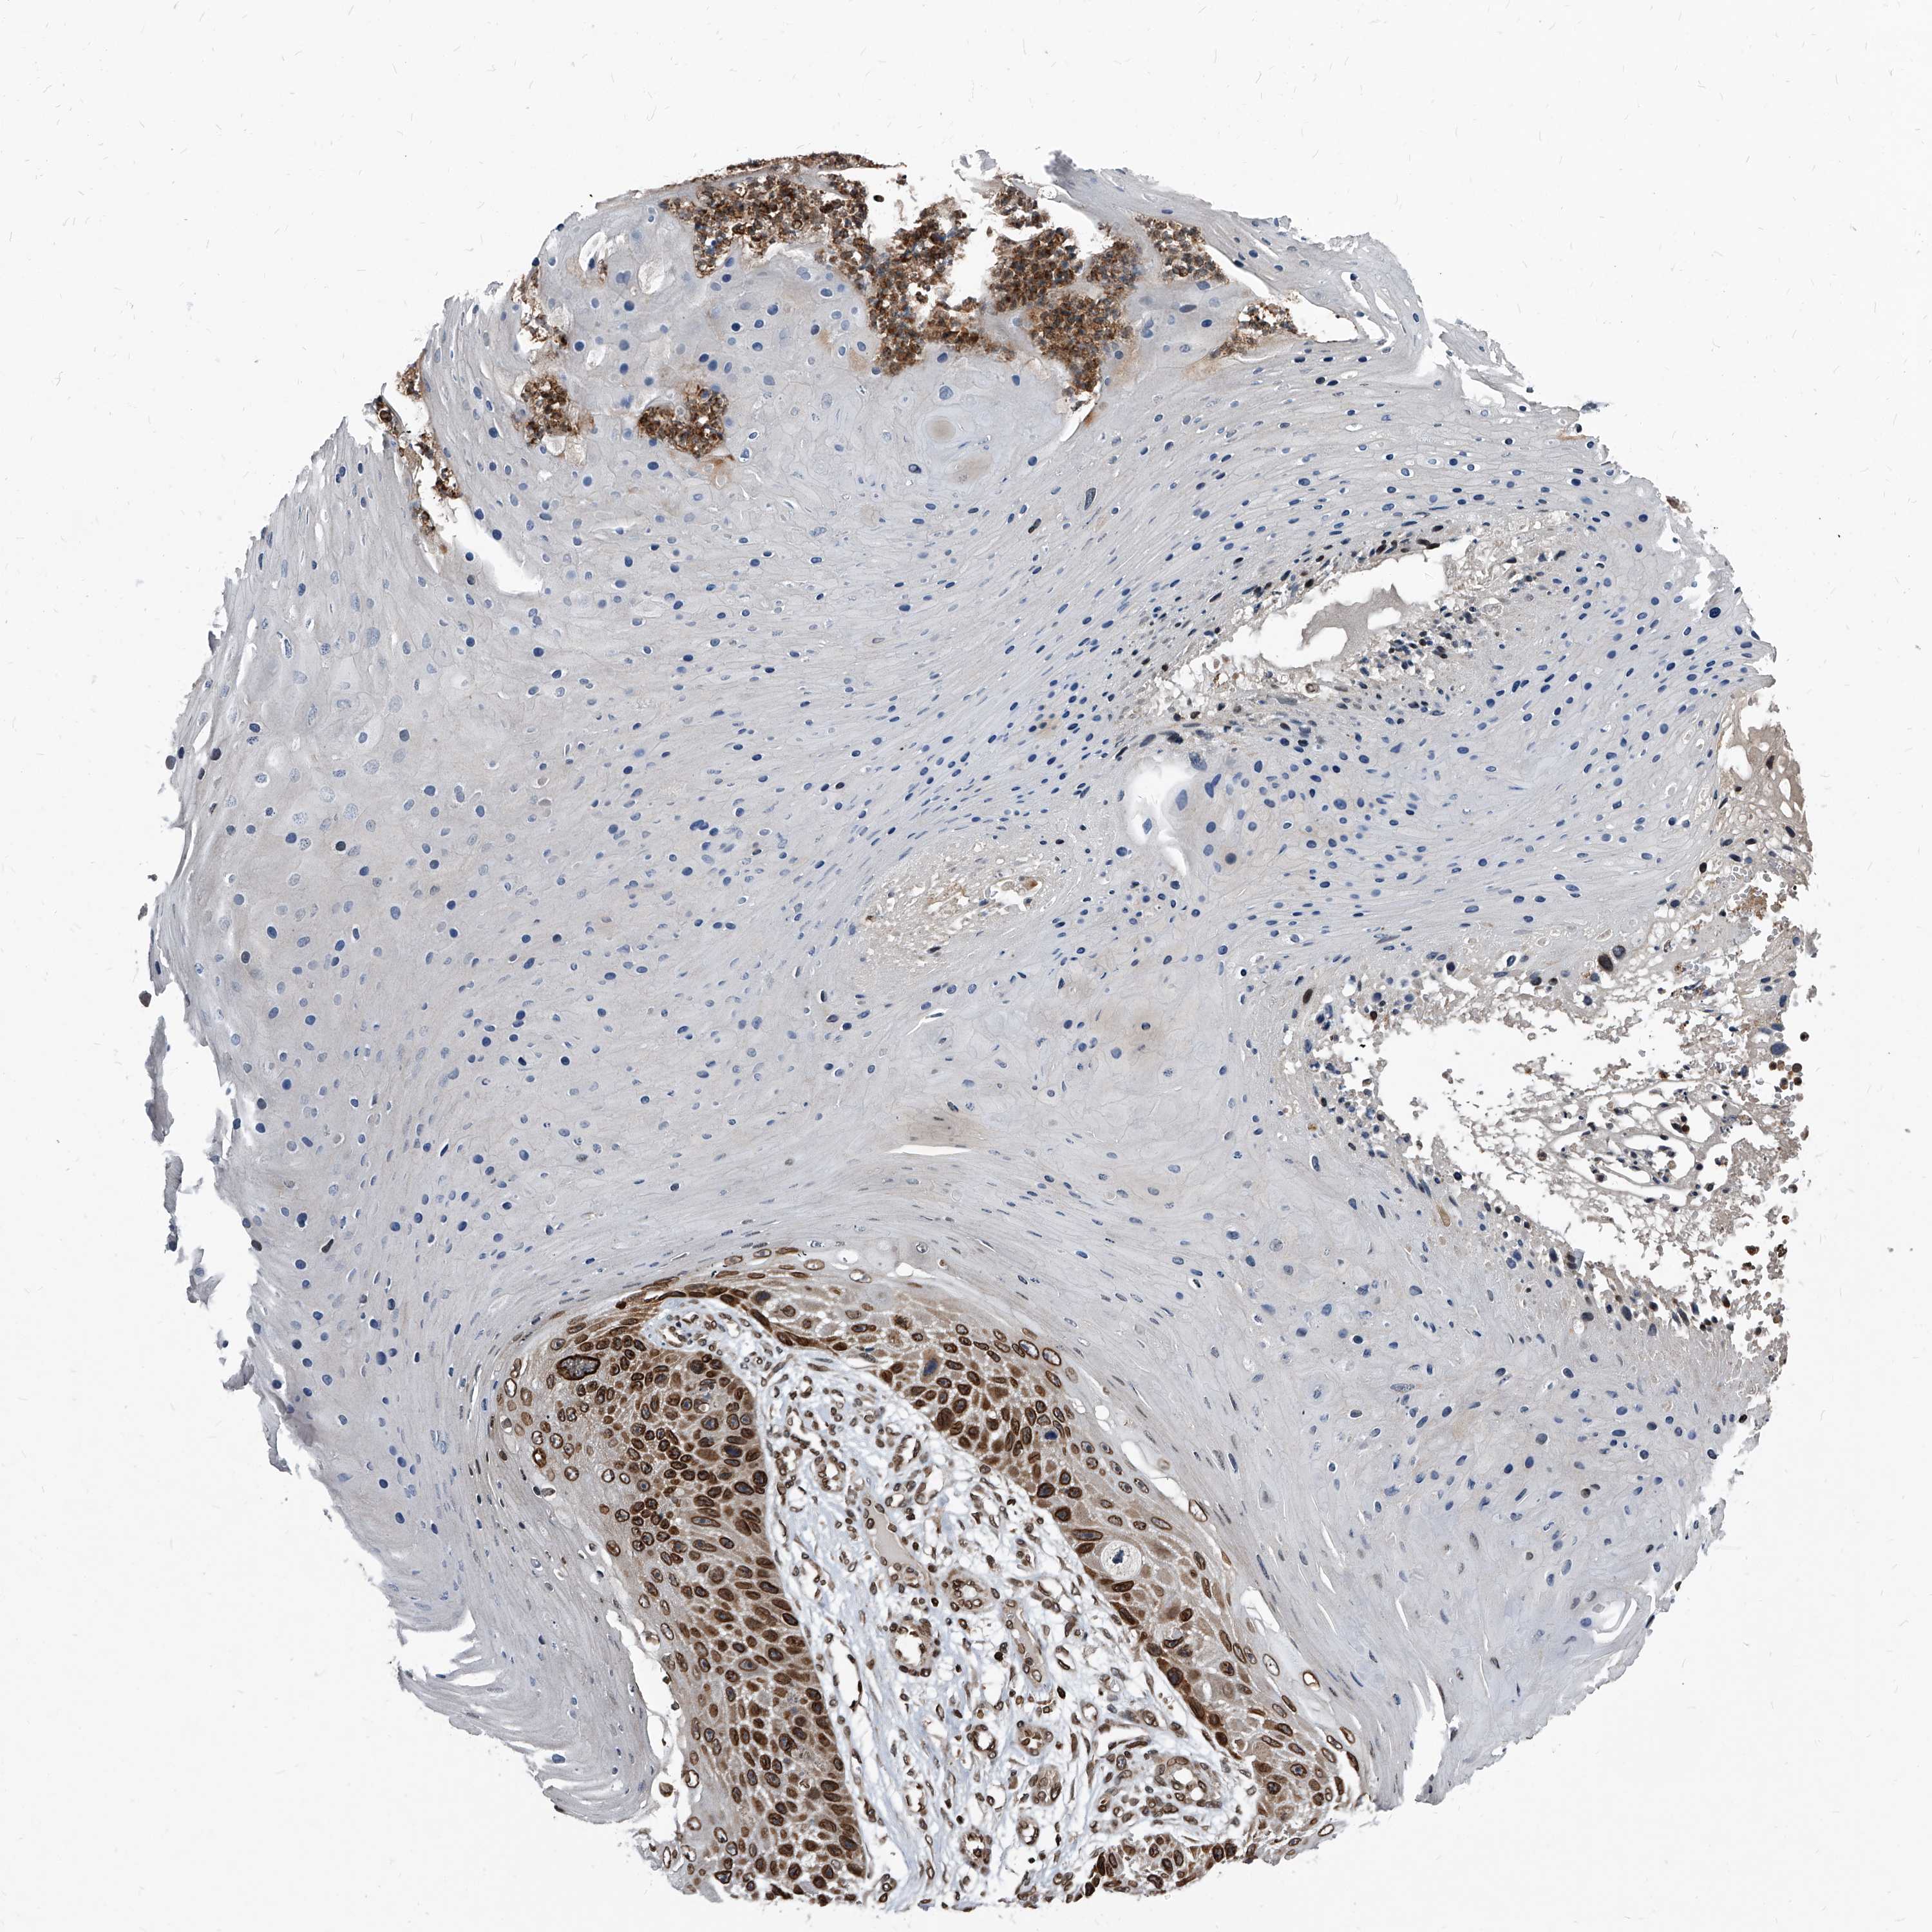

Basal cell and squamous cell cancer

SKIN CANCER - Protein expressioni

A mouse-over function shows sample information and annotation data. Click on an image to view it in a full screen mode. Samples can be filtered based on level of antibody staining by selecting one or several of the following categories: high, medium, low and not detected. The assay and annotation is described here.

Each image is clickable and will lead to virtual microscopy that enables deeper exploration of all samples and also displays staining intensity scores, fraction scores and subcellular localization as well as patient and tissue information for each sample.

Antibody HPA029619

Squamous cell carcinoma, metastatic, NOS

Squamous cell carcinoma, NOS